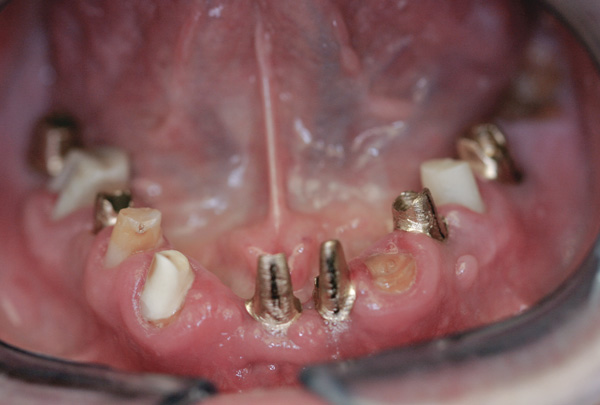

Background: This patient had a failing maxillary dentition and refused to wear a removable prosthesis. A staged approach was employed to retain some of his natural tooth abutments, and recession was noticed at the time of the impression for the second group of implants. Figure 1 shows the patient following insertion of the first set of implant custom abutments; the adjacent natural teeth are still present to support the provisional bridge. Seven months later, as shown in Figure 2, those first-stage custom abutments exhibited evidence of 1 mm to 3 mm of recession.

Figure 11 Recession evident around first-stage abutments following adjacent extractions and second-stage implant placement.

Figure 11